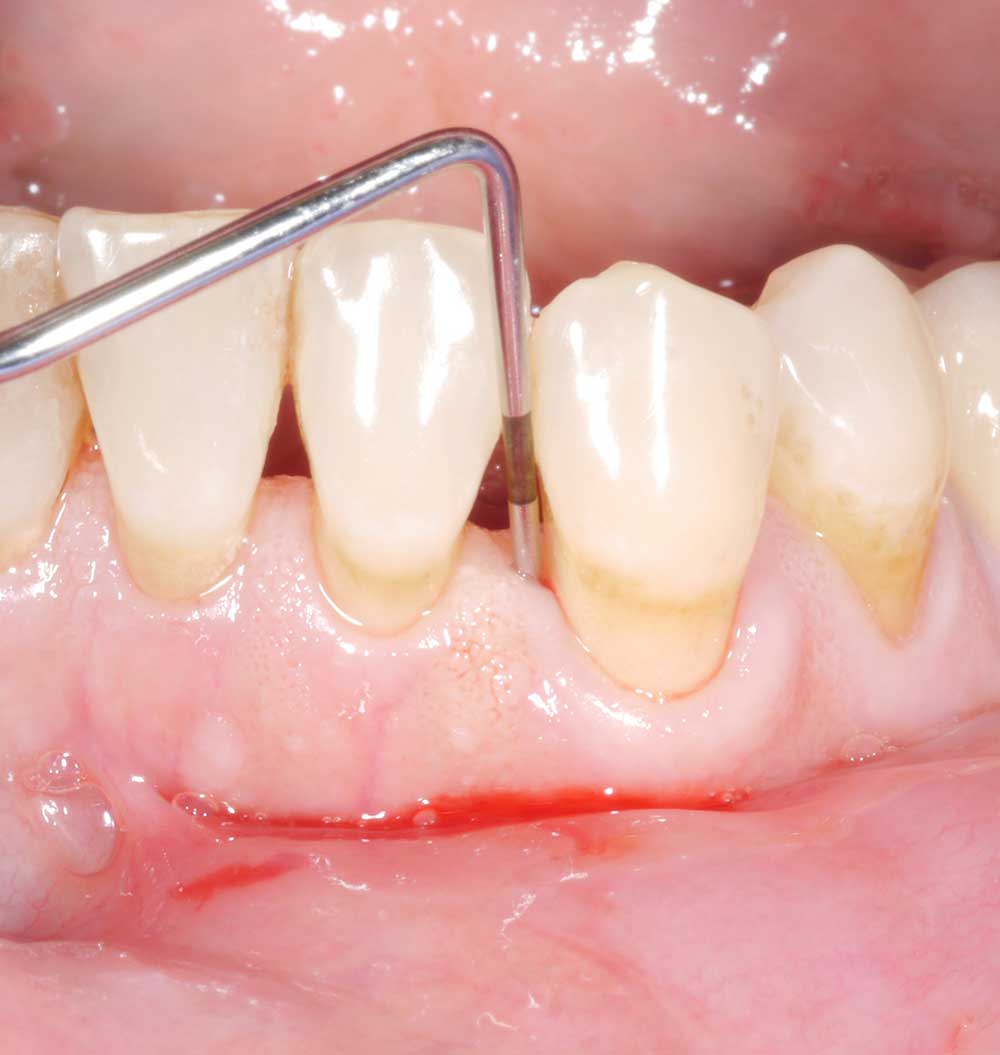

Regarding the second question: either type of probe can be used – metal or plastic. However, depending on the type of prosthetic restoration, the plastic probe may have certain advantages. In certain cases (e.g. patients with overhanging crown designs or implant-retained complete dentures), the slight flexibility of the plastic probe provides better access and therefore probably more accurate measurements. The Figure shows just such a case, of a patient with an implant-retained complete denture (a). Figures (b) and (c) show that probing depth differs substantially depending on the type of probe used. Whereas probing with the metal probe yielded a depth of 3 mm (b), the measurement for the plastic probe was substantially higher (c) – 8 mm! After removal of the prosthetic restoration (Figures [d] and [e]), the probing depths are the same for both types of probe – approx. 10 mm. Depending on the access and the patient’s prosthetic restoration, thought should be given in the dental practice as to whether the slight flexibility of a plastic probe might provide better access and thus more accurate measurements.